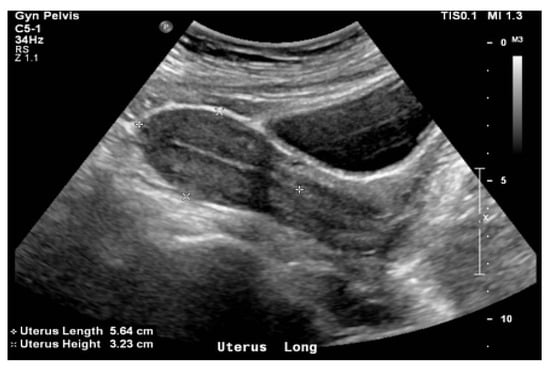

| TAUS | Transabdominal ultrasound |

- Van Dyk, S.; Narayan, K.; Fisher, R.; Bernshaw, D. Conformal Brachytherapy Planning for Cervical Cancer Using Transabdominal Ultrasound. Int. J. Radiat. Oncol. 2009, 75, 64–70. [Google Scholar] [CrossRef] [PubMed]

- Mahantshetty, U.; Khanna, N.; Swamidas, J.; Engineer, R.; Thakur, M.H.; Merchant, N.H.; Deshpande, D.D.; Shrivastava, S. Trans-abdominal ultrasound (US) and magnetic resonance imaging (MRI) correlation for conformal intracavitary brachytherapy in carcinoma of the uterine cervix. Radiother. Oncol. 2011, 102, 130–134. [Google Scholar] [CrossRef] [PubMed]